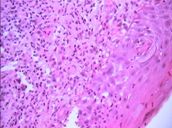

El estudio histopatológico (Nº 03-129) realizado en la Cátedra de Anatomía Patológica General y BMF de la Facultad de Odontología, informó que se trataba de una ampolla subepitelial. El epitelio se mantenía en áreas adosado a la membrana basal. El conjuntivo presentaba un infiltrado inflamatorio linfocitario, con neutrófilos, plasmocitos, abundantes mastocitos y neovasos (Fotos 8 – 10).

Foto 9 Infiltrado de linfocitos, neutrófilos y plasmocitos

Foto 10 Presencia en conjuntivo de mastocitos y neovasos. Alteración de células basales